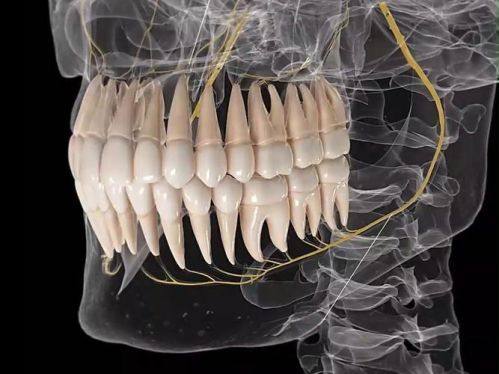

1. 种植牙技术:拥有专精的医生团队,能够根据患者的口腔情况和需求,选择合适的种植体,为患者提供稳定、持久的种植牙解决方案。

2. 牙齿矫正:提供多种矫正方式,如舌侧矫正等,医生会根据患者的牙齿状况制定个性化的矫正方案,有效改善牙齿排列不齐的问题。